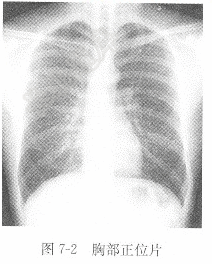

试题详情单项选择题男性,40岁,咳嗽1周,X线胸片见图7-2,X线诊断为( )。A、气胸B、肺癌C、肺结核D、正常正确答案:关注下方微信公众号,搜题查看答案热门试题题见图6-3。 心电图的应用范围肾囊肿胃、十二指肠溃疡硬膜下血肿如何判断房性期前收缩代偿间歇是否完全?阵发性室性心动过速题见图6-2。 活化部分凝血活酶时间(AFTT)心房颤动题见图6-14。 甲种胎儿球蛋白(AFP)阵发性室上性心动过速题见图6-7、图6-8。 血液酸碱度(pH)γ-谷氨酰转移酶(GGT)肾癌房性期前收缩伴室内差异性传导与室性期前收动脉血氧分压(PaO2)原发性肝癌